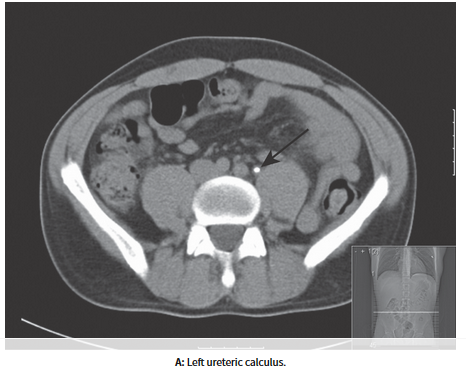

What is a CT-KUB?

CT of kidney, ureter and bladder - best diagnostic test available